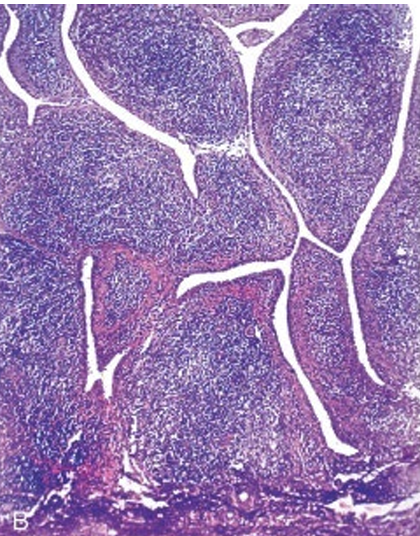

What disease is this

Hashimoto’s disease